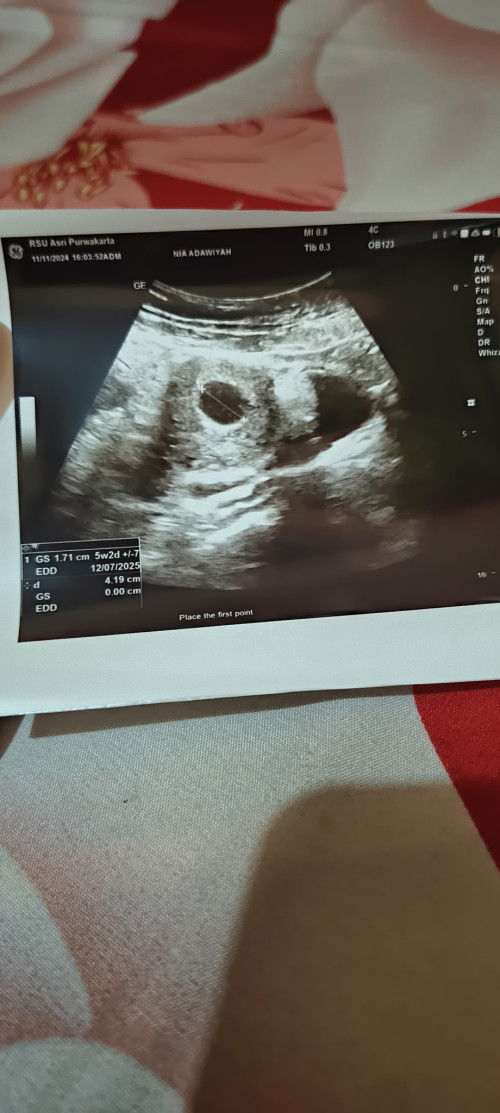

Hamil 8 minggu

Bunda ada yang ngalamin gk ? Kalau dihitung dari hpht usia kandungan ku 8 minggu tpi pas diusg baru 5w2d terus masih keliatan kantungnya aja belum keliatan janinnya🥺itu normal gk ya bun🙏tolong bantu infonya dong bun🥺